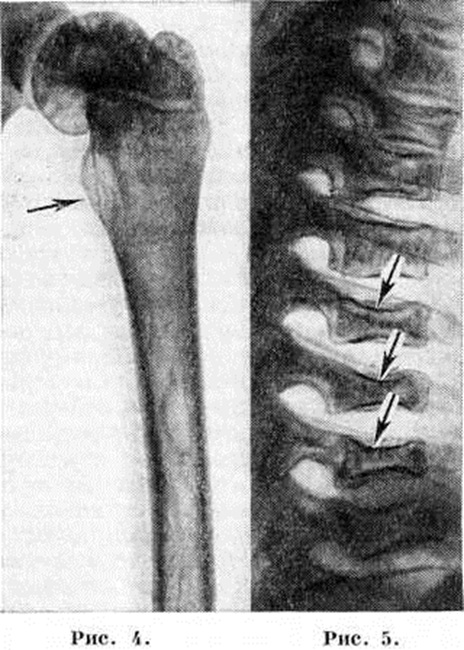

Наиболее часто изменения обнаруживают в длинных трубчатых костях и позвоночнике. Первое место по частоте поражения занимает дистальная половина бедра, где выявляют характерное веретенообразное или булавовидное вздутие кости (рисунок 2 и 3) с истончением коркового слоя, которое часто сочетается с грубо-ячеистой структурой, внутрикостными обызвествлениями, отдельными очагами деструкции и иногда с эностальным склерозом кости. Периостозы, как правило, не развиваются; иногда могут наблюдаться обширные краевые деструкции, сопровождающиеся периостозами. В головке бедренной кости образуются асептические некрозы по типу болезни Пертеса со свойственной данному заболеванию стадийностью процесса и исходами (смотри полный свод знаний Пертеса болезнь). Может наблюдаться утолщение шейки бедра (рисунок 4) с образованием coxa vara.

Патологический переломы тел позвонков могут привести к клиновидной их деформации. Сохранность межпозвоночного диска позволяет исключить туберкулёзный характер поражения. В ряде случаев развивается множественное поражение тел позвонков, сопровождающееся уменьшением их высоты и приводящее к снижению роста больного — системная бревиплатиспондилия (рисунок 5).

Рис. 4. Рентгенограмма бедра ребёнка 10 лет при болезни Гоше: выражено утолщение шейки бедренной кости (указано стрелкой).

Рис. 5. Рентгенограмма грудного отдела позвоночника ребёнка 10 лет при болезни Гоше: выражена бревиплатиспондилия (уплощение тел позвонков — указано стрелками).